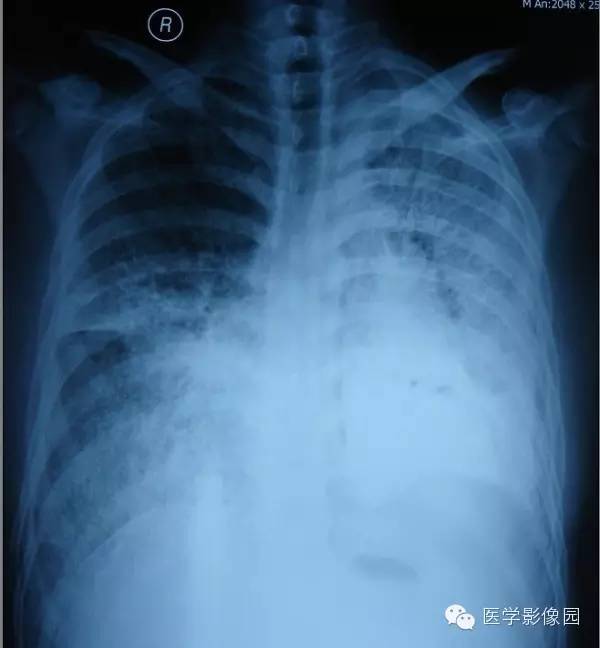

【病例】尘肺1例X线及CT影像表现

男性,36岁,镀锌工作史1年。

小结节影:多为双肺弥漫性或散在小结节影,表现为类圆形影,边界清晰,以中下肺为主,背侧多见。

肺门改变: 肺门影增大,肺门多伴点状或蛋壳状钙化。

肺纹理:扭曲及变形改变。